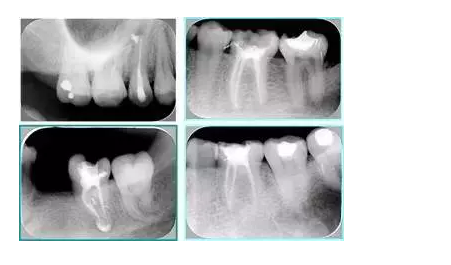

常見不良根管充填物有干髓、塑化、塑化 + 根充和不良根充。

( 1 )干髓。

干髓治療時,開髓后髓腔里注入甲醛甲酚 FC 灌髓,三聚甲醛固定,髓室底放置三聚甲醛緩慢釋放,進(jìn)行根管無害化處理。髓腔緩慢壞死,機(jī)體代償出現(xiàn)根管鈣化。如果患者在封閉腔出現(xiàn)出現(xiàn)病變,由于髓腔鈣化,根管堵塞嚴(yán)重,檢查治療比較困難。

左圖和上圖為干髓治療后牙齒,齲齒疏通后進(jìn)行根管充填。

( 2 )塑化。

( 3 )塑化 + 根充。

如圖為塑化加根充處理后牙齒 X 線片。

6. 鈣化

常見有修復(fù)性鈣化和增齡性鈣化。下面為根管鈣化 X 線片。